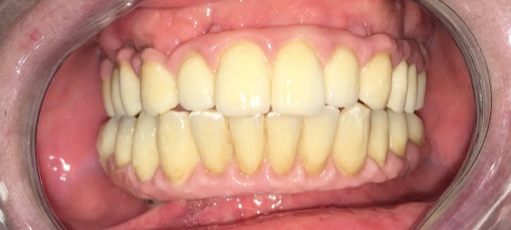

III fase, posizionamento della protesi sugli impianti: fase chirurgica: con il supporto del Laboratorio Odontotecnico Design Dentale (www.designdentale.it) e della Dottoressa Daniela Gasparini, entro poche ore saremo in grado di fissare gli elementi dentali direttamente sugli impianti inseriti durante la prima fase chirurgica. Ogni protesi è personalizzata e il risultato estetico sarà assolutamente naturale: questo è possibile anche grazie allo studio del caso preliminare effettuato pre-intervento con l’ausilio di foto ed impronte di ogni singolo paziente e tecnologia digitale CADCAM.

La protesi che ti verrà consegnata il giorno dell’intervento, anche se provvisoria, dovrà essere quanto più possibile perfetta e rispecchiare in pieno i desiderei e le aspettative del paziente

Il Chirurgo sarà sempre affiancato da un protesista esperto in protesi da carico immediato e dai tecnici del laboratorio che realizzano manufatti da carico immediato da tantissimi anni e con la massima qualità. Per fare in modo che vada tutto alla perfezione, non sono importanti solo gli impianti ma anche le protesi fisse che vengono avvitate sugli stessi.

Anche per le protesi definitive, che avranno la barra in titanio o cr-co di rinforzo, ti verrà rilasciata la certificazione 93/42 e la garanzia dal laboratorio sulla durata delle stesse.